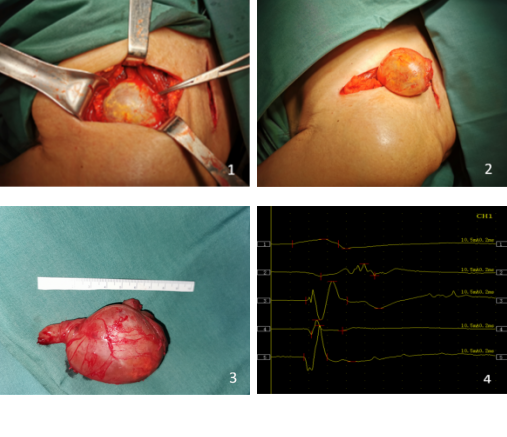

刘大爷住院后,考虑到手术如果采取切断锁骨的方式,会对锁骨的损伤非常大,陈步国主任组织科内人员进行术前讨论,分析手术中可能存在的困难及风险,制定出另一套损伤小、恢复快的方案——不切断锁骨,直接采取“锁骨上、下联合切口”,通过锁骨上、下切口于锁骨下做通道取出肿物手术方案。次日,手术按时进行,术中探查见肿物与臂丛神经相连,上肢的一些主要的动、静脉都在肿物的下方。手术风险性非常大,稍有不慎,就会损伤血管造成大出血的状况。术中按照术前拟定的手术方案,采取锁骨上、下切口,通过锁骨下隧道方式仔细剥离肿物上神经束,这就要求主刀医生具有丰富的手术经验和过硬的显微外科技术。经过3个半小时的努力,手术顺利完成。取出的肿物经过测量,大小在7cm×5cm×5cm,竟然比一个鸡蛋还要大。肿物取出后用术中肌电图生理检测臂丛神经呈现正常电生理表现,手术过程中很好地保护了臂丛神经。术后肿物送病理检查再次明确诊断为神经鞘瘤。